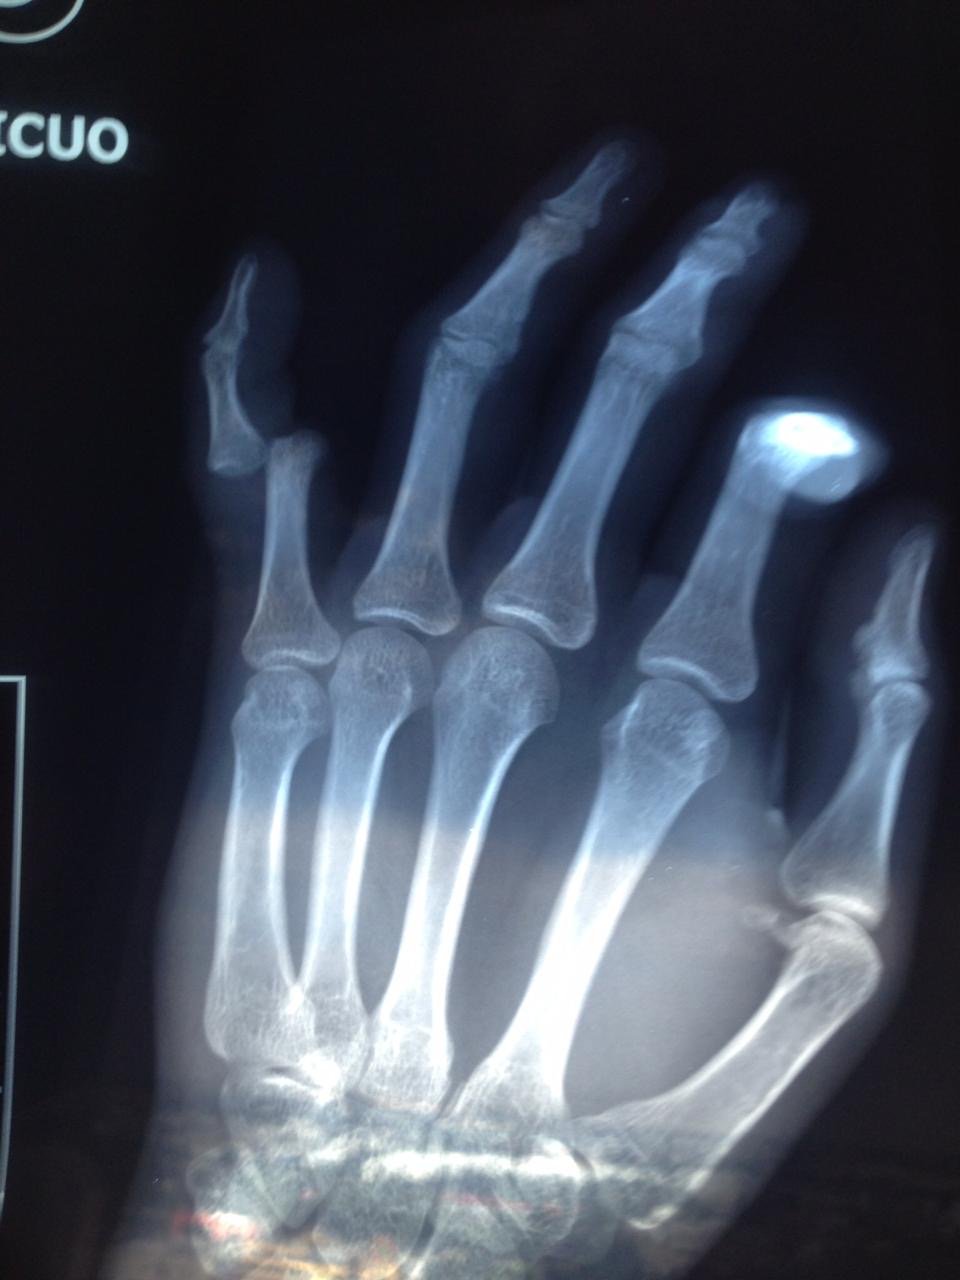

• Secuelas de: fracturas, fisuras, luxaciones, esguinces, tendinitis, tendinosis,  y desgarres musculares.

• Post operados de: Columna, Hombro, Codo, Muñeca, Mano y Dedos, Cadera, Rodilla, Tobillo y Pie